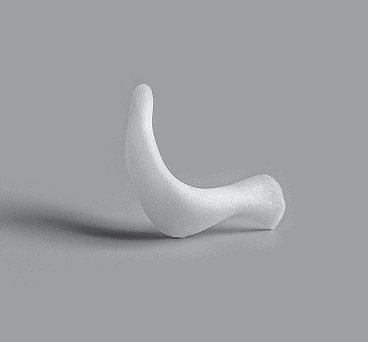

Enophtalmos Wedge